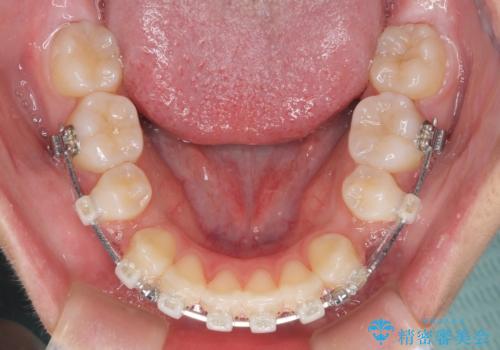

- クリアブラケット

- 2年4ヶ月

当初は八重歯やデコボコが一番気になっていましたが、抜歯矯正により口元の突出感が改善されるにつれ、口の閉じやすさを実感するようになってきました。

部活動で調整来院に来られないことがしばしばあり、期間は予定よりもかかりましたが、きれいに仕上げることができました。